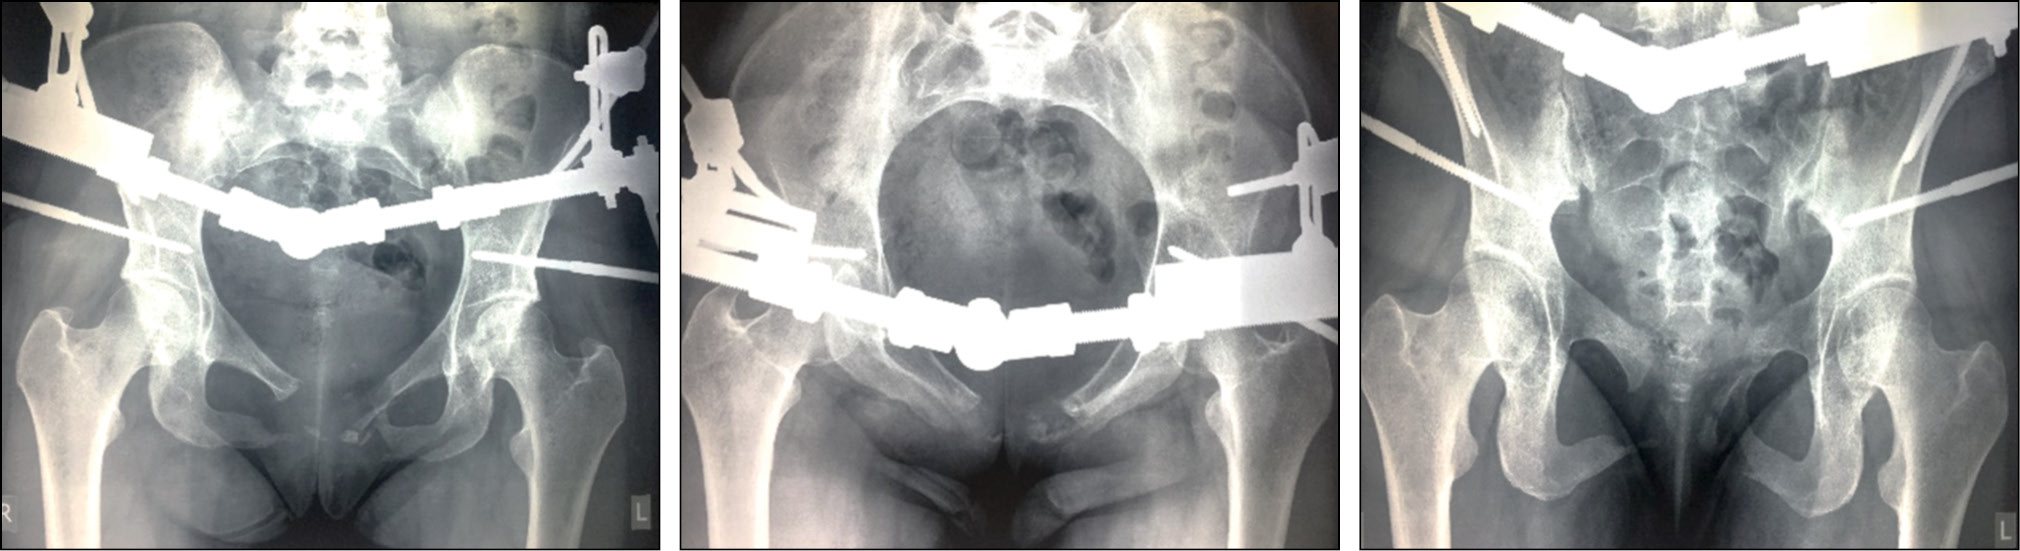

На 1-е сут после операции у пациентки нормализовалась температура тела (до 36,7 °C). Боль, иррадиирующая в низ живота, поясницу и промежность, купировалась. Вертикализация пациентки началась на 3-е сут после вмешательства. Спустя 12 нед был произведён демонтаж аппарата внешней фиксации. Боль в лонной, ягодичной области, иррадиирующая в низ живота, спину, пах, промежность, полностью купировалась. При контрольном осмотре спустя 4 мес после операции (рис. 3, 4) отмечен удовлетворительный исход, пациентка вернулась к нормальному образу жизни.

Рис. 3. Рентгенограммы пациентки С. через 4 мес после операции.

Fig. 3. Radiographs of patient S. 4 months after operation.